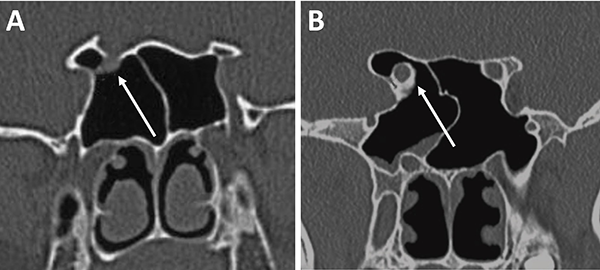

El grado de neumatización de etmoides posterior es variable. Se debe identificar si existe hiperneumatización del mismo, con extensión de celdillas a región superior y lateral se seno esfenoidal, variante que conocemos como celdas de Onodi. Su relevancia radica en mantener durante el intraoperatorio un adecuado corredor hacia la hipófisis, y evitar una “falsa vía”, con potencial lesión intracraneal (fig. 15).

Figura 15: Hiperneumatización de etmoides posterior. A) TC corte sagital; B) TC corte coronal, obsérvese la celdilla de Onodi (asterisco blanco).